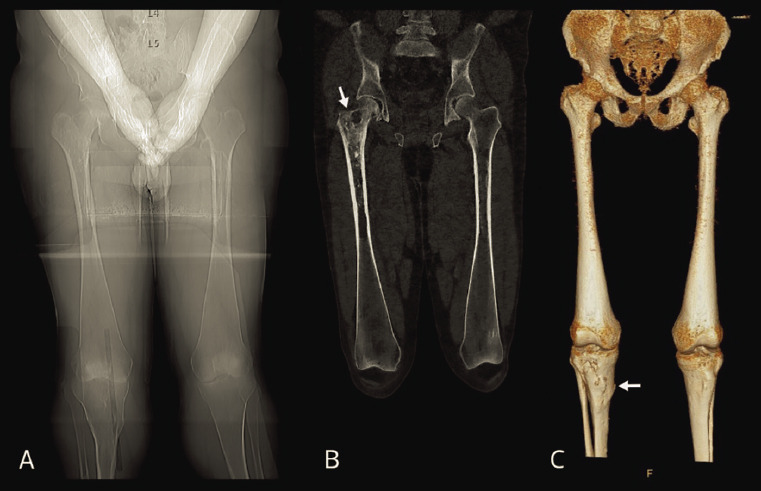

The Erlenmeyer Flask Deformity on Computed Tomography.

计算机断层扫描中的锥形烧瓶变形。